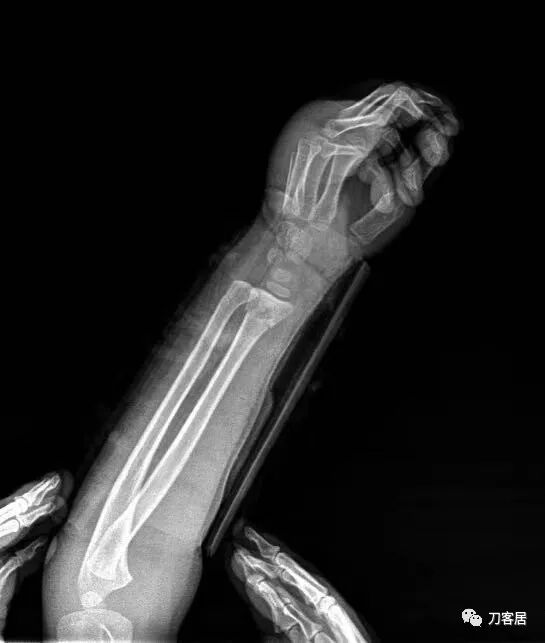

病例2. 没有提供具体患者性别和年龄,为尺桡骨中段双骨折。

图1. 骨折后,复位前。尺桡骨正位片。

图2. 骨折后,复位前,尺桡骨侧位片。

图3. 手法复位后小夹板外固定,尺桡骨侧位片。

图4. 手法复位后,小夹板外固定,尺桡骨正位片。

图5. 骨折愈合后尺桡骨正位片,虽有残余畸形,但功能良好。

图6. 骨愈合后尺桡骨侧位片。功能良好。